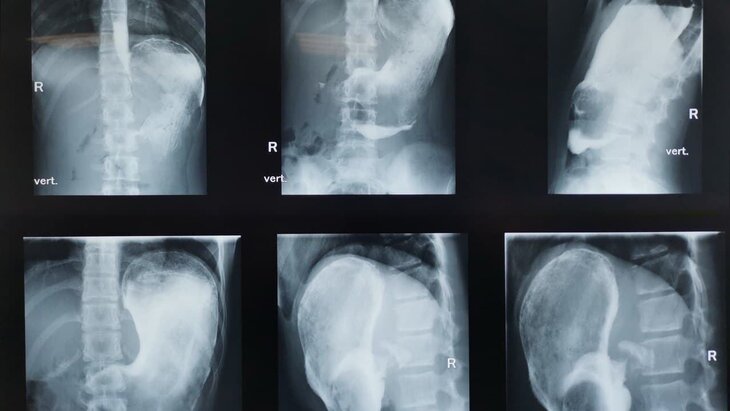

Фото: пресс-служба департамента здравоохранения Москвы

В Москве врачи детской городской клинической больницы имени Башляевой извлекли из желудка 11-летней девочки плотный ком волос весом один килограмм. Об этом сообщает Агентство "Москва" со ссылкой на пресс-службу столичного Депздрава.

Девочка пожаловалась на усилившиеся за две недели боли в животе, тошноту и снижение аппетита. При проведении гастроскопии врачи обнаружили массивное образование внутри желудка ребенка.

"Пациентка призналась, что имеет привычку обсасывать кончики волос. Врачи незамедлительно начали проведение срочного оперативного вмешательства, в ходе которого в просвете желудка обнаружилось плотное инородное тело больших размеров", – рассказали в пресс-службе.

В результате операции 25-сантиметровый трихобезоар был извлечен.